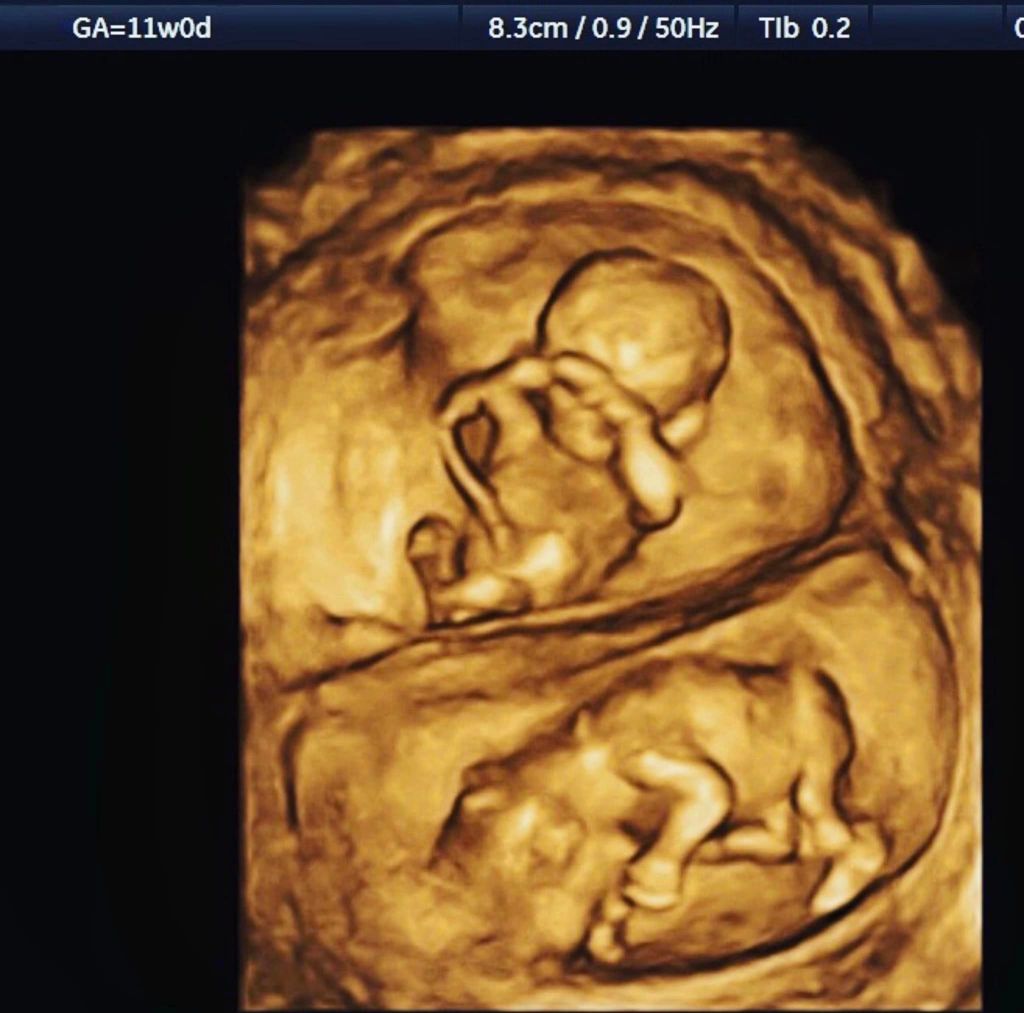

像第二張圖在高解析度超音波下你看到的就是單絨毛膜雙羊膜(看不懂沒關係等你當婦產科醫師我就會教你)